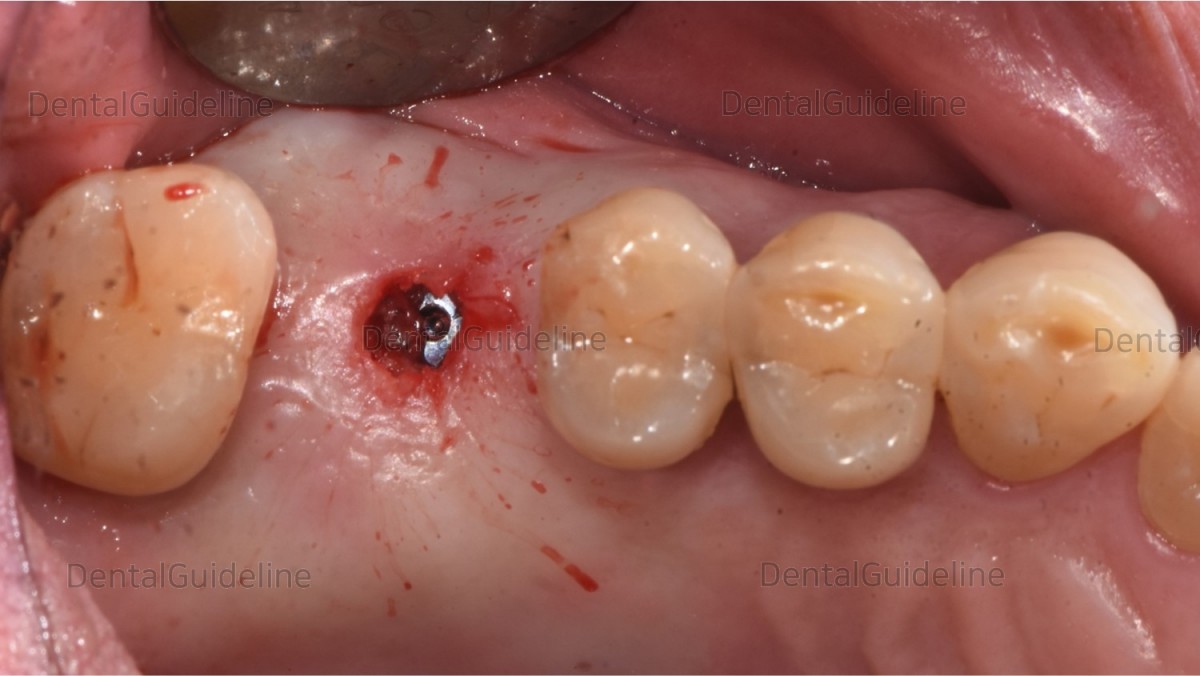

6. The fixation was exposed using a tissue-punching instrument.

![]()